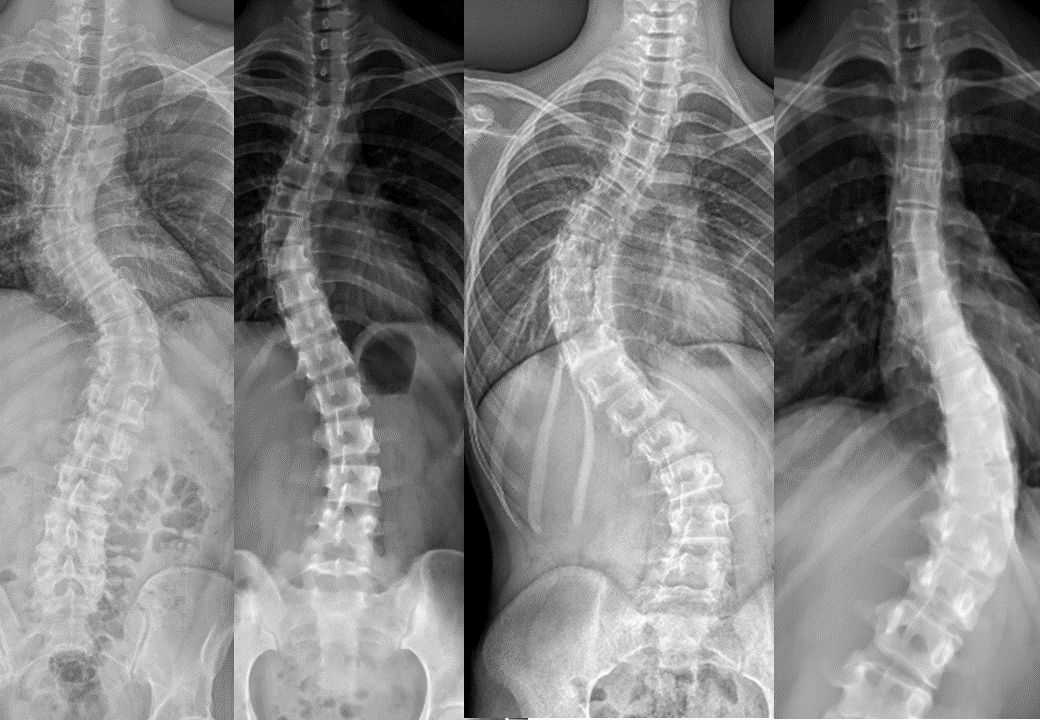

脊椎側彎(Scoliosis)主要表現為脊椎向側面異常彎曲,並伴隨脊椎本身的旋轉變形。醫學上通常以 Cobb angle(柯柏角度) 來衡量側彎的嚴重程度,當角度大於10度,即可被診斷為脊椎側彎。

脊椎側彎嚴重度分級(Cobb角度)